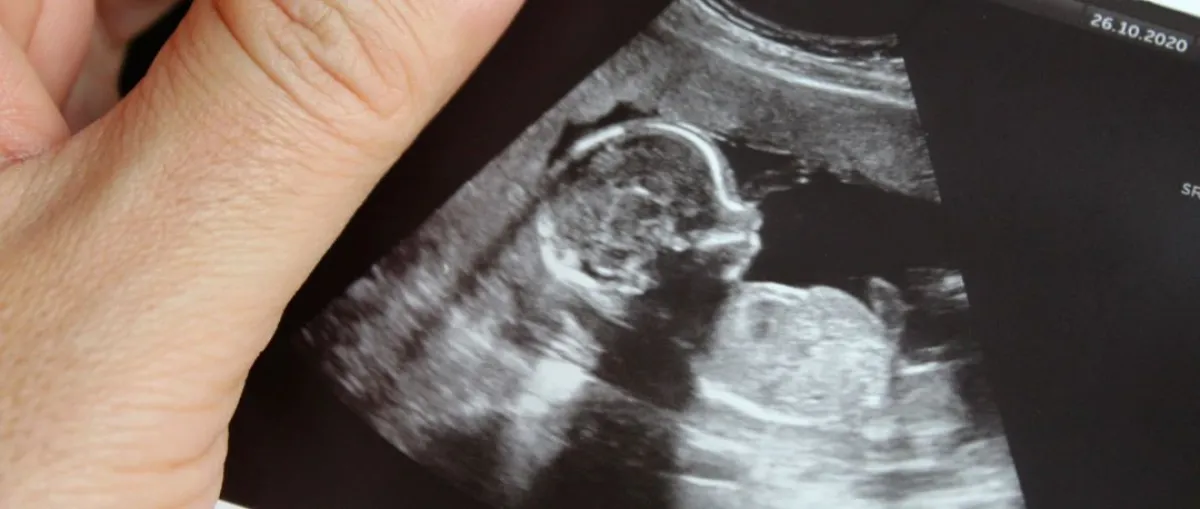

- وقد توصل باحثون في دراسة نشرتها المجلة الأمريكية للتغذية السريرية، أن اضطراب أنماط النوم الليلي عند الأطفال قد يشير إلى أن الجهاز العصبي المركزي لديهم لم يتطور بشكل كامل خلال مرحلة الحمل، وأن الأمهات اللواتي تناولن المحار خلال الحمل قد تطور لدى الأجنة الجهاز العصبي المركزي، وحظين بأطفال ينامون جيداً ولديهم معدلات ذكاء أعلى من قرنائهم.

- وكشفت الدراسة نفسها أن الاختبارات التي تُعْنَى بفهم الكلمات من قبل الأطفال في عمر 15 شهراً، قد كشفت أن الأطفال الذين جاءوا من أمهات أكلن المحار مرة في الأسبوع على الأقل قد أعطوا معدلات 7% أعلى من أطفال الأمهات اللاتي لم يتناولن المحار أبداً طيلة فترة الحمل.

- كما أن المأكولات البحرية قد تسبب التسمم بالزئبق لدى الحوامل في الشهر الثالث من الحمل، ومن بينها المحار، خاصة في حال تناوله نيئاً، ولذلك يُفضَّل عدم تناول المحار في الأشهر الأولى الثلاثة من الحمل، حيث تشكل خطراً على تطور نمو دماغ الجنين الذي يتشكل في هذه الفترة بالذات.

- كما أن من أعراض تسمم الجنين بالزئبق بعد الولادة أنه قد يُصاب بتلف في الدماغ والأعصاب ، ولا تتم ملاحظته عند ولادة الطفل، بل يظهر بعد فترة من خلال تأخر الطفل في النمو حسب جداول النمو ومعدلاته الطبيعية مثل أن تظهر لدى الطفل علامات تأخر في المشي واضطرابات الكلام أو مشكلات التركيز والتذكر، وكذلك اضطرابات في بعض الحواس مثل مشكلات في السمع والبصر.